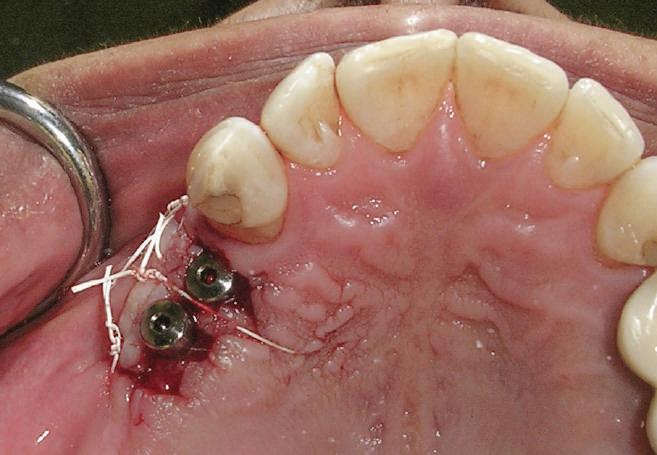

Reprepararea intraorală a bonturilor Acest pacient prezenta dentiţia maxilară compromisă, refuzând proteza mobilizabilă. Prin abordarea în etape, se menţin o parte din bonturile dentare naturale; s-a observat recesie în momentul amprentării pentru cel de-al doilea grup de implanturi.

Fig. 1 prezintă pacientul după inserarea primului set de bonturi implantare individualizate; dinţii naturali adiacenţi

sunt încă prezenţi pentru a susţine puntea provizorie.

Şapte luni mai târziu (fig. 2), acele bonturi individualizate din prima etapă au manifestat semne de recesie de 1-3mm. Atitudine: S-a decis reprepararea intraorală a tuturor bonturilor (fig. 3), astfel încât toate marginile bonturilor să fie la nivelul sau sub marginea gingivală (de notat că 1.1. şi 2.1. au fost submersaţi ulterior pentru a avea sprijin implantar deplin).

Deşi reprepararea a îmbunătăţit marcat estetica finală, a necesitat aplicarea şnurului de retracţie, amprente noi şi turnări noi.

Un caz separat dar similar ilustrează în figurile 4 și 5 reprepararea intraorală a bontului.

Cazul (1): Reprepararea intraorală a bonturilor Figurile

1. Aspect după inserarea primului set de bonturi implantare individualizate.

2. După 7 luni, bonturile individualizate din prima etapă au prezentat recesie de 1-3mm.

3. Bonturile repreparate intraoral.

Alt caz (1) Figurile

4. După osteointegrarea implantului 2.4., s-a observat recesia în etapa de amprentare a implantului 2.5.; s-a decis reprepararea marginilor bontului individualizat CAD/CAM 2.4. Înainte de preparare s-a aplicat şnur de retracţie pentru a evita lezarea ţesutului şi a îmbunătăţi vizibilitatea dintelui 2.3. şi a marginii bontului implantar individualizat. Aşa cum era de aşteptat, recesia a fost mai mare de-a lungul versantului distal al bontului 2.4. adiacent locului de extracţie vindecat/cu implantul mai nou.

5. Bontul individualizat aplicat (2.5.) cu bontul repreparat anterior (2.4.). Nu a survenit recesie nouă de o perioadă de peste 3 ani.